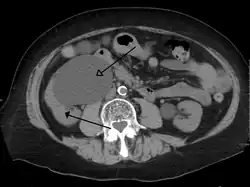

CT scan of bilateral hydronephrosis due to a bladder cancer -

Massive hydronephrosis as marked by the arrow. -